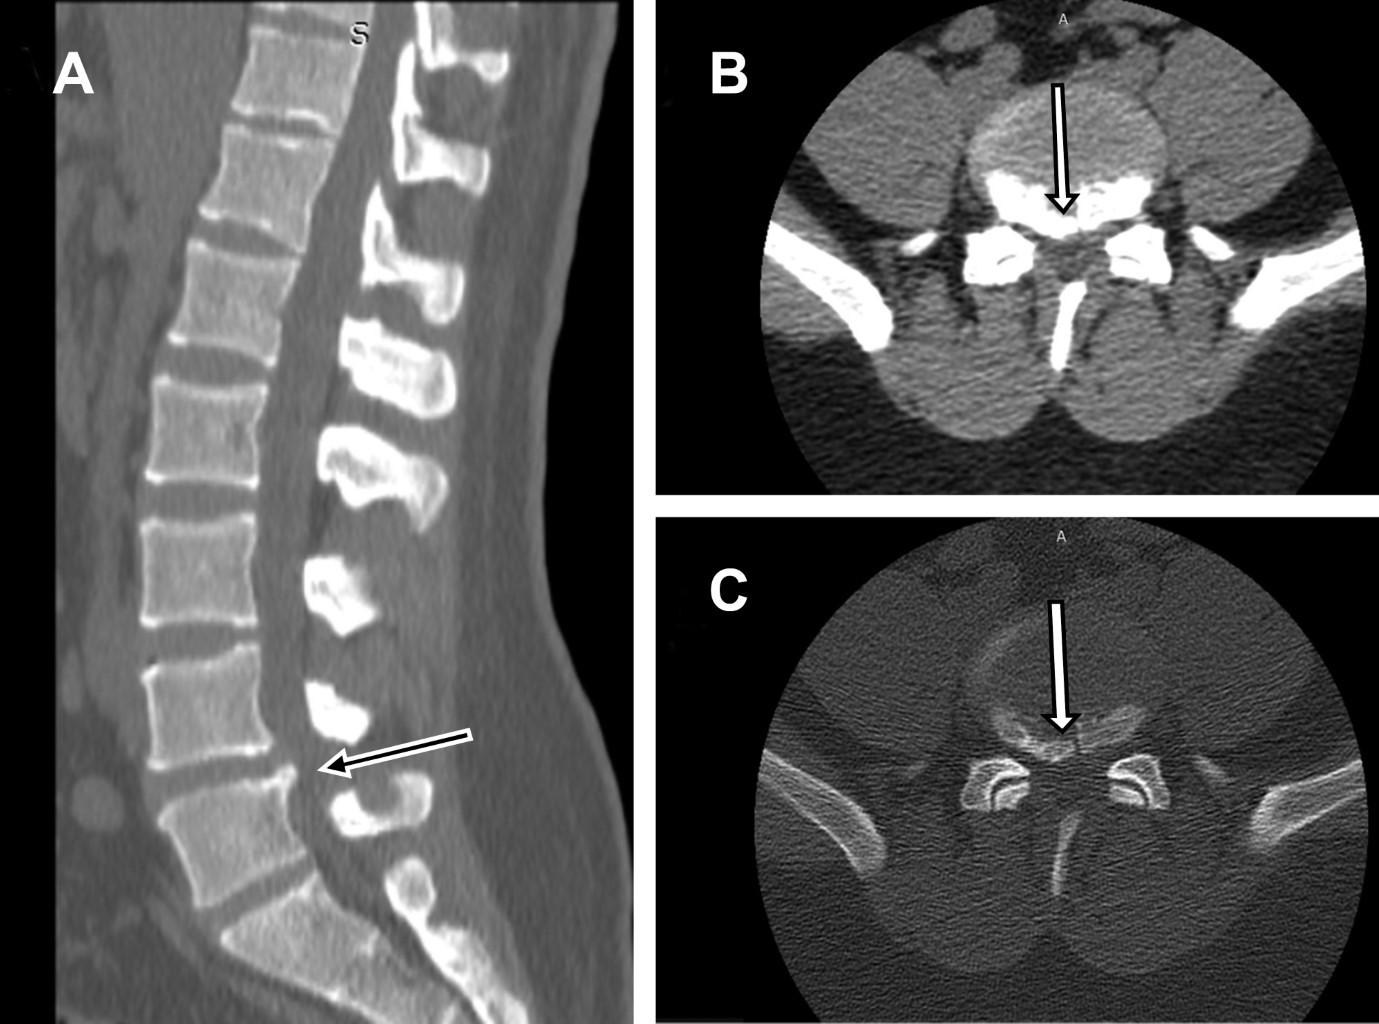

Masculino de 23 años sufrió accidente de tráfico, colisionando su motocicleta contra vehículo en movimiento, chocando contra el piso a 8 m del percance, presentando dolor lumbar severo; a la exploración se encontró: dolor severo a la palpación de región lumbar, exquisito a la percusión de apófisis espinosas L4 y L5, paresia 2/5 en músculos inervados por raíces L4, L5 y S1 izquierdos, disminución de reflejos rotuliano y aquíleo izquierdos, pulsos y llenado capilar normales con diagnóstico de posible fractura vertebral L4-L5 y compresión radicular L4-L5 S1. Se efectuó tomografía computarizada (Figura 1) y resonancia magnética de región lumbar (Figura 2), encontrando: fractura del borde posterior inferior de L4, con extrusión masiva de material discal L4/L5 de localización paracentral izquierda que obstruye agujero de conjunción. Se efectuó laminectomía y discoidectomía, y fue dado de alta hospitalaria. A 21 días de seguimiento, paciente asintomático con recuperación de fuerza muscular, sensibilidad y reflejos normales.

Figura 1